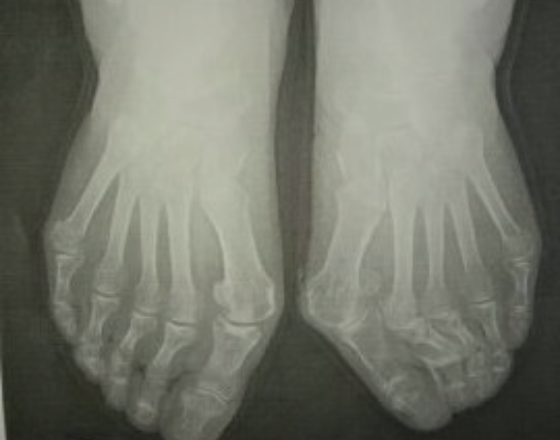

外反母趾など足の指付近の関節の変形のほとんどの症状は靴に起因し、足に合うことの無い靴が原因で発症し、悪化していきます。

数多くの外反母趾などにお困りの方に足や外反母趾などに合わせ靴を作ってきました。

そのためには・・・足のカタチと変形具合に合わせ靴を作ることで多くの方がお困りになっている足の痛みの緩和と減少、解消にいつなげることが出来ます。